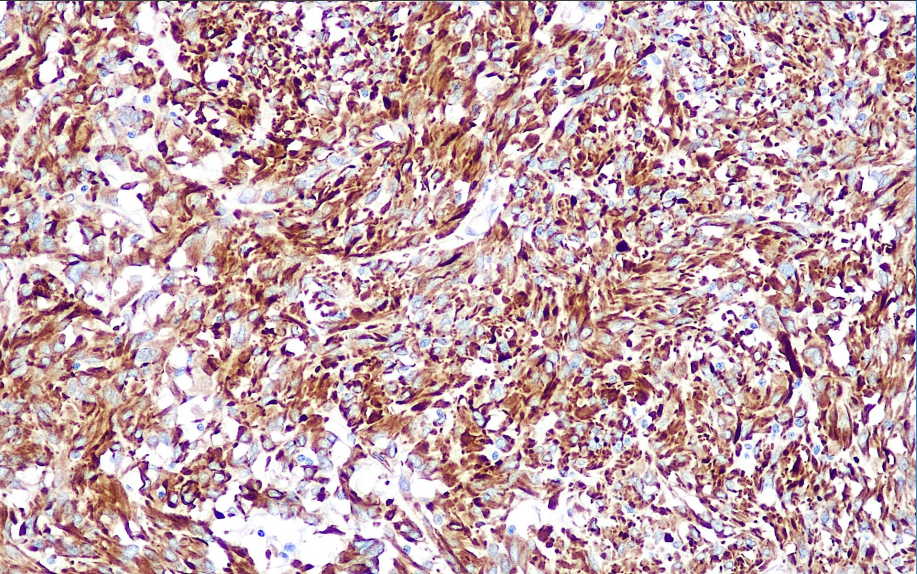

Positive control: Gastrointestinal mesenchymal stromal tumor

Nestin is a kind of intermediate filament protein, which exists in neuroepithelial stem cells with multidirectional differentiation potential during embryonic development. This antibody has a strong specificity and is mainly used to determine whether the tumor cells are of primitive neuroectodermal origin, and the positive sites are cytoplasm and protrusions, such as primitive neuroectodermal tumors, medulloblastomas and other naïve tumor cell components are positive.

Nestin antibody reagents can specifically bind to Nestin molecular antigens. Immunohistochemical kits containing Nestin antibody reagents are suitable for the precise diagnosis of glioblastoma and melanoma (primary melanoma and metastatic melanoma).